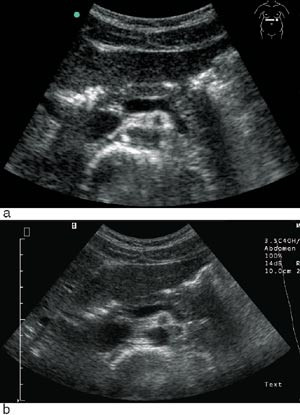

Undersøkerens totale tilfredshet med bruk av denne skanneren var: 0 lite tilfreds, 8 % litt tilfreds, 11 % moderat tilfreds, 36 % meget tilfreds, 45 % svært tilfreds. Skanneren var ikke bare egnet til «enkle» problemstillinger, men kunne også gi tilfredsstillende svar på mer kompliserte kliniske og bildemessige utfordringer (fig 3, fig 4).

I 81 % av tilfellene fant vi tilfredsstillende bildekvalitet (e-fig 1) med bruk av mobil skanner, til tross for at det hos 28 % av pasientene var dårlig innsyn. Noen syntes at skjermen var for liten og at dette utgjorde en begrensende faktor. Et ultrasonogram hvor man sammenlikner opptak gjort på samme pasienter med Sonosite 180 mot Siemens Elegra demonstrerer hvor bra bildekvaliteten er (fig 2). Gjennomsnittlig tidsbruk under skanning var 7 ± 3 minutter. I 83 % av tilfellene ble den aktuelle kliniske problemstillingen adekvat besvart med mobil skanning, i fire tilfeller (11 %) ble det ansett som nyttig å skanne pasienten med et stasjonært ultralydapparat i tillegg. Utredning og/eller behandling av pasientene ble i 39 % av tilfellene endret som følge av skanning.